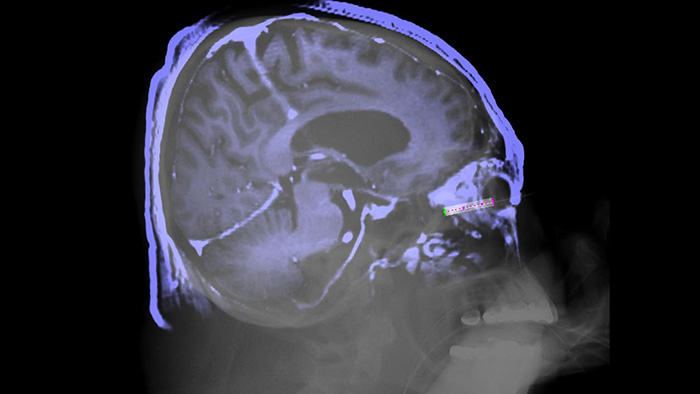

XperGuide offers live 3D image needle guidance, letting you bring percutaneous needle procedures into the Hybrid OR. It overlays live fluoroscopy and 3D soft tissue imaging data from previously acquired CT or MR scans or Philips XperCT, providing information on the needle path and target.